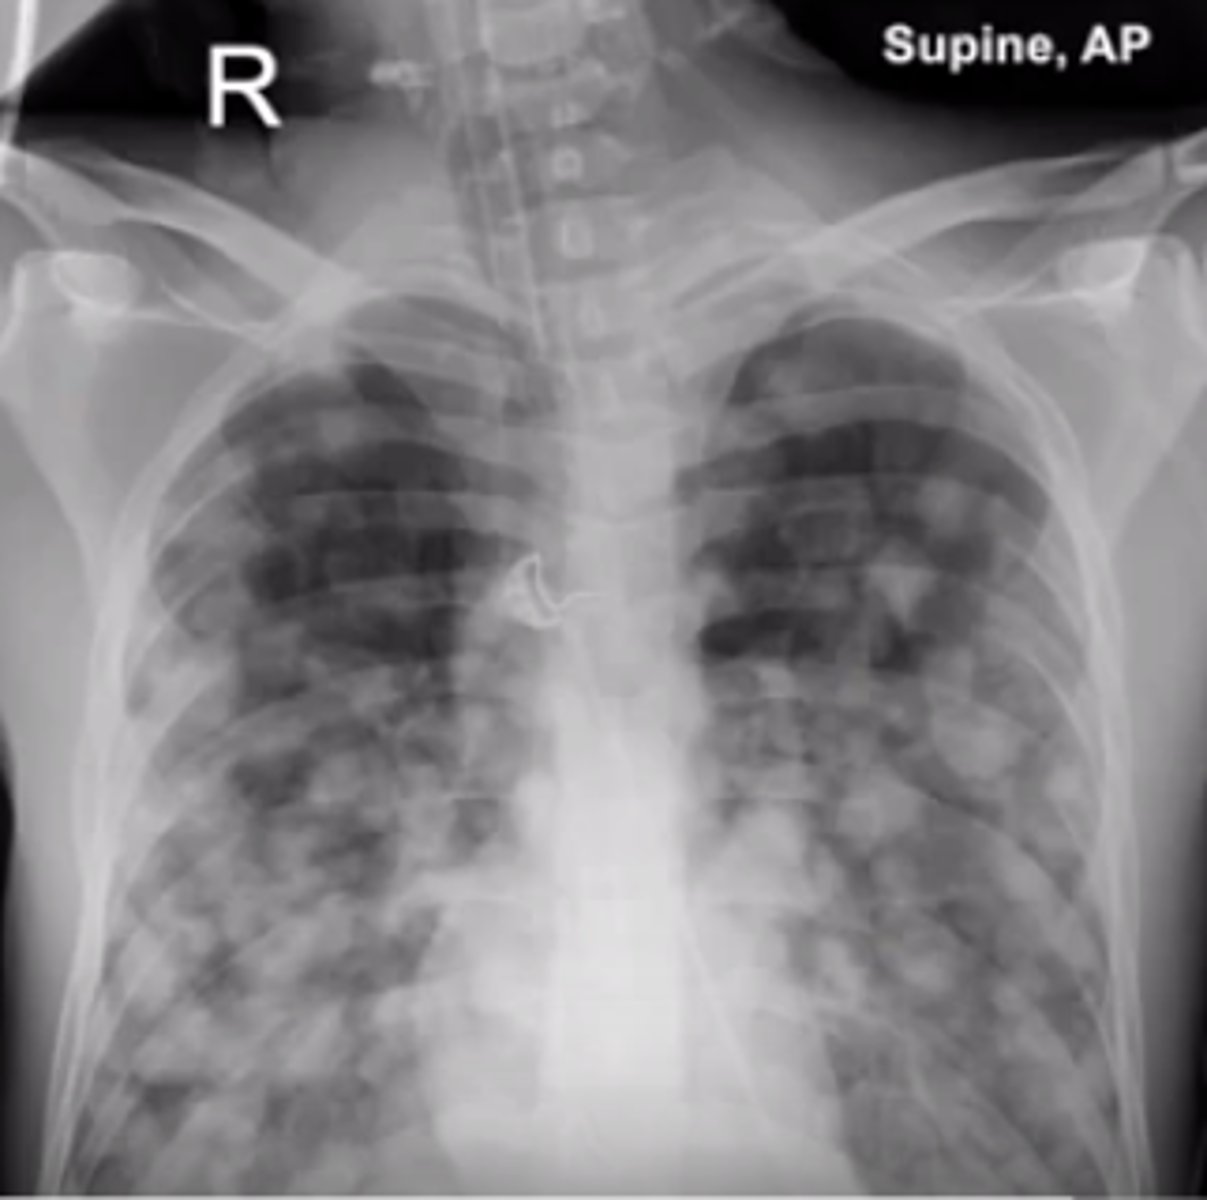

lungs : cannonball metastasis

what other cancers may produce a cannonball metastasis appearance?

testicular choriocarcinoma, renal cell carcinoma, prostatic adenocarcinoma